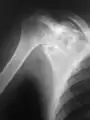

A variety of imaging studies can be used to diagnose chondroblastoma, with radiographs being the most common.[10][8] Laboratory studies are not considered useful.[14] Classical chondroblastoma (appearing on long bones) appears as a well-defined eccentric oval or round lytic lesion that usually involves the adjacent bone cortex without periosteal reaction.[10][13] A sclerotic margin can be seen in some cases.[10][13] For long bone chondroblastomas the tumor is typically contained to the epiphysis or apophysis but may extend through the epiphyseal plate.[10][13] Chondroblastomas are usually located in the medullary portion of bones and can, in some cases, include the metaphysis.[10][13] However, true metaphyseal chondroblastomas are rare and are typically the result of an extension from a neighboring epiphyseal legion.[10][13] Most lesions are less than 4 cm.[10] A mottled appearance on the radiograph is not atypical and indicates areas of calcification which is commonly associated with skeletally immature patients.[10] Additionally, one-third of all cases involve aneurysmal bone cysts which are thought to be the result of stress, trauma or hemorrhage.[10] In cases involving older patients or flat bones, typical radiographic presentation is not as common and may mimic aggressive processes.[10][13]

Other imaging techniques involve computed tomography (CT), magnetic resonance imaging (MRI), and bone scans, which may be helpful in determining the anatomical boundaries, associated edema, or biological activity of the chondroblastoma, respectively.[8][10] MRI studies may show extensive oedema around the lesion and show variable T2 signal intensity.[15]

Chondroblastoma was first described in 1927 as a cartilage-containing giant cell tumor by Kolodny but later characterized by Codman in 1931.[10][12] Codman believed chondroblastoma to be an "epiphyseal chondromatous giant cell tumor" in the proximal humerus.[10][7] This view was changed later by a comprehensive review completed by Jaffe and Lichtenstein in 1942 of similar tumors in other locations than the proximal humerus.[10][12] They re-defined the tumor as a benign chondroblastoma of the bone that is separate from giant cell tumors.[11] However, chondroblastoma of the proximal humerus is still sometimes referred to as Codman’s Tumor.[10][7][12]